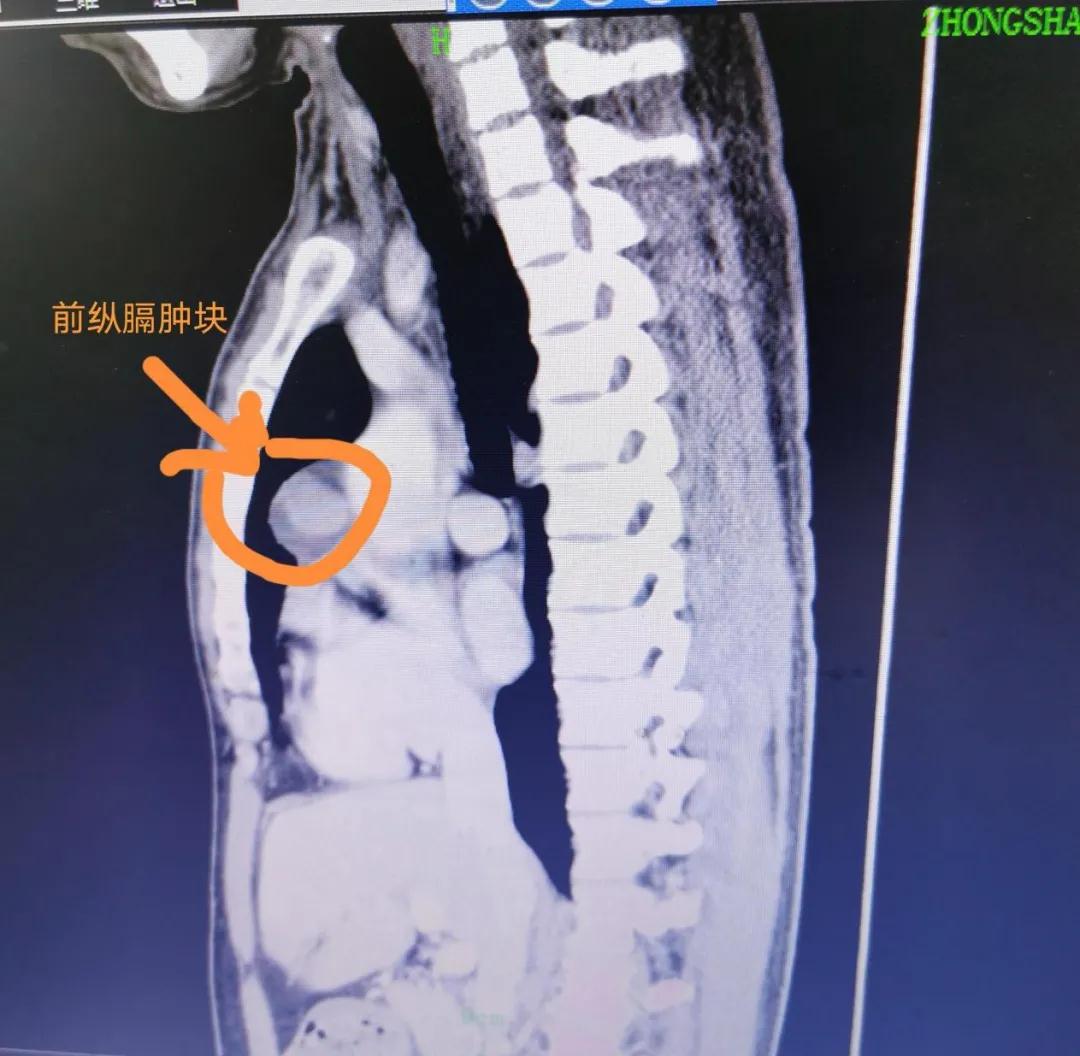

随后,他来到中山某医院就诊,经过胸部CT检查发现,胸部前纵隔有鸡蛋大小的肿瘤,而且紧靠心脏,挤压非常重要的大血管。

根据陈先生的症状表现及影像结果,胸外科医生考虑存在胸腺瘤的可能。

经过约1个半小时的微创手术操作,成功摘除前纵隔肿瘤,并清扫前纵隔脂肪组织。幸运的是,经过病理切片组织标本送检结果显示,陈先生前纵隔肿瘤为良性胸腺瘤。